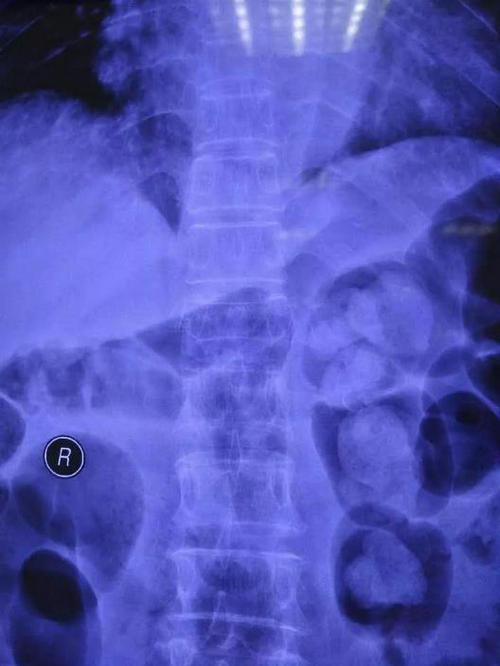

张长江主任指示付卫平,余耀坤两位医师迅速完善相关检查,明确诊断,排除手术禁忌症。各项检查结果都证实了张长江主任的判断——胸12椎体压缩骨折。

▲ 患者术前正侧位影像